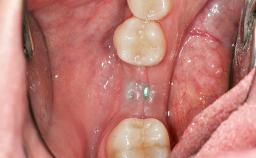

In 1983, a 51-year-old non-smoking patient was referred for the treatment of moderate chronic periodontitis. At the initial examination, 47% of sites exhibited probing depths of 4 to 6 mm. Periodontal therapy consisted of initial periodontal treatment including oral-hygiene instructions and supra- and subgingival debridement, followed by periodontal surgery to eliminate residual pockets.